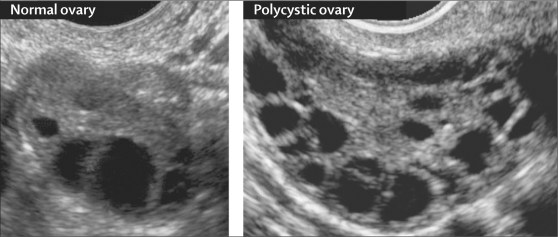

PCOS is a condition whereby small ‘cysts’ develop on a woman’s ovaries. In actual fact, these ‘cysts’ are not actually cysts per se, but are ovarian follicles which contain eggs. A healthy young woman will usually have about 5-10 follicles in each ovary, however, in the case of PCOS, each of the ovaries contain more than 10-12 follicles. Although these follicles are a sign of abundance in egg numbers, they cause the body to have hormone imbalances. Because hormones are chemical messengers, responsible for triggering various different processes in our bodies, when a hormone imbalance occurs it causes detrimental chain reactions.

In order to diagnose PCOS, your doctor will begin by asking you a series of questions about your health, symptoms and menstrual cycles. This will be followed by a physical exam, which will look for excessive body hair and high blood pressure, as well as take note of your body mass index (BMI). Next, some of your blood will be drawn to test your blood sugar, insulin and other hormone levels. Finally, you may have a pelvic ultrasound to look for cysts on your ovaries. Early diagnosis and treatment is crucial, as it can help you to control the unpleasant symptoms of PCOS, as well as prevent long-term health problems.